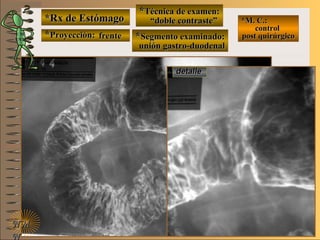

*Rx de Estómago*Rx de Estómago

**Proyección:Proyección:

**Técnica de examen:Técnica de examen:

**Segmento examinado:Segmento examinado:

*M. C.: control*M. C.: control

post quirúrgicopost quirúrgico

NMNM

detalledetalle

frentefrente

““doble contraste”doble contraste”

unión gastro-yeyunalunión gastro-yeyunal

A-A-El examen es normal o patológico?El examen es normal o patológico?

Examen patológico de estómago con técnicaExamen patológico de estómago con técnica

de doble contraste, localizada, post quirúrgicade doble contraste, localizada, post quirúrgica

en proyección de frenteen proyección de frente

B-B-La patología es congénita o adquirida?La patología es congénita o adquirida?

Patología adquiridaPatología adquirida

D-D-La misma es neoplásica o no neoplásica?La misma es neoplásica o no neoplásica?

Patología adquirida orgánica neoplásicaPatología adquirida orgánica neoplásica

E-E-Puede describir la o las imágenes patológicas?Puede describir la o las imágenes patológicas?

Se identifica la anastomosis de la unión gastro-Se identifica la anastomosis de la unión gastro-

yeyunal (Billroth II) lugar donde residiban lasyeyunal (Billroth II) lugar donde residiban las

lesiones neoplásica, se valoran también el diá-lesiones neoplásica, se valoran también el diá-

metro de la “boca” y la integridad de la suturametro de la “boca” y la integridad de la sutura

C-C-Dicha patología es orgánica, funcional o mixta?Dicha patología es orgánica, funcional o mixta?

Patología adquirida orgánicaPatología adquirida orgánica